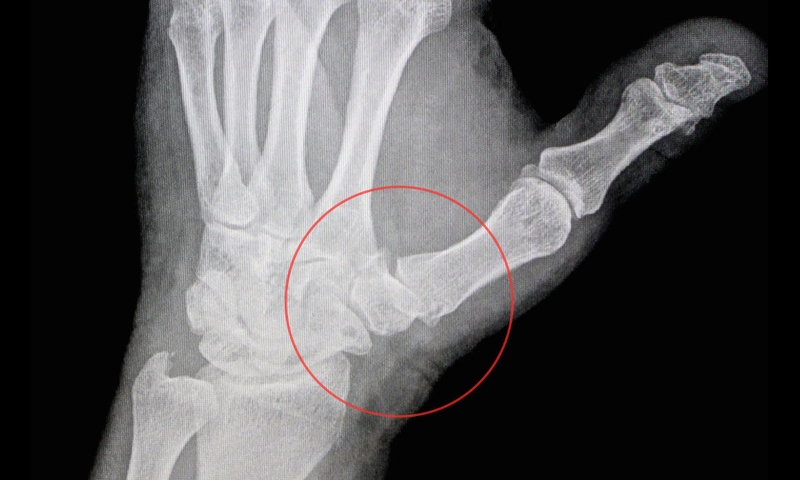

• Chụp X-quang.

Sau đó, để xác nhận chẩn đoán chính xác, bác sĩ sẽ yêu cần bạn thực hiện một số xét nghiệm cần thiết:

Dựa vào những kết quả xét nghiệm và các thông tin ban đầu, bác sĩ sẽ xác định nguyên nhân gây đau khớp 2 ngón tay cái. Tùy thuộc vào nguyên nhân mà người bệnh sẽ được chỉ định phác đồ điều trị phù hợp.